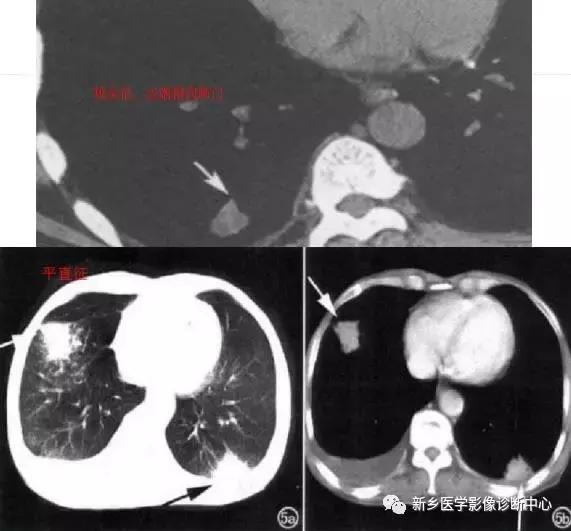

单发胸膜间皮瘤

常发于胸壁腋缘,单发、多发良性,无症状或局部钝疼。圆形或半球形密度影,基底位于胸膜,与胸壁成钝角,密度均匀。

4个不同的胸膜间皮瘤: